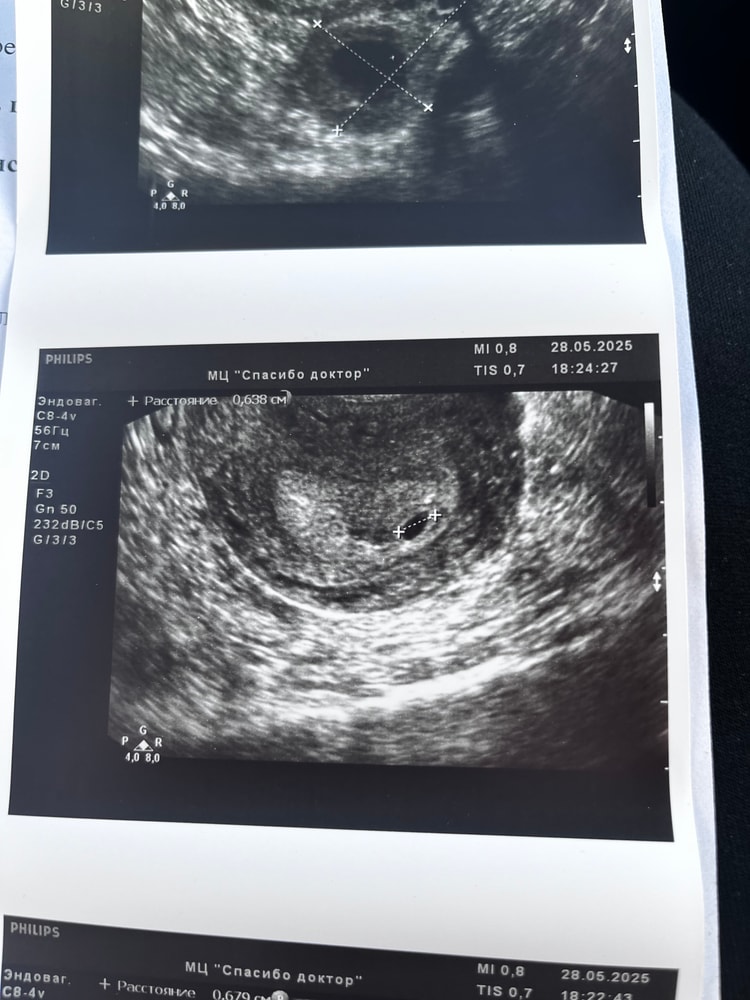

неделю назад была на узи, поставили беременность раннего срока, эмбрион еще не лоцировался. два дня назад увидела странные коричневые выделения, поехала в жк (но у нас горе жк где даже узи не сделали, просто прописали дюфастон)

сегодня попала на узи, сказали срок 6 недель, сердцебиение 148 уд/мин, небольшая отслойка и угро